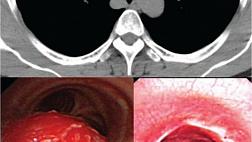

Пациенту была проведена полностенная резекция опухоли. После маркировки и подслизистой инъекции был сделан дугообразный разрез по ходу пищевода с полностенной резекцией (рис. 2 — A, B, C). Для закрытия дефекта использовалась новая петля LeCamp™ Endoloop Device (Leo Medical Co., Ltd., Китай; рис. 1 — D; 2 — D, E) и эндоскопические клипсы. Патоморфологическое исследование удаленной опухоли (рис. 2 — F) подтвердило диагноз «лейомиома». Послеоперационный период протекал без осложнений. При исследовании через 2 месяца нарушений проходимости пищевода не выявлено (рис. 2 — G).

image003.jpg

Рисунок 2 [1].